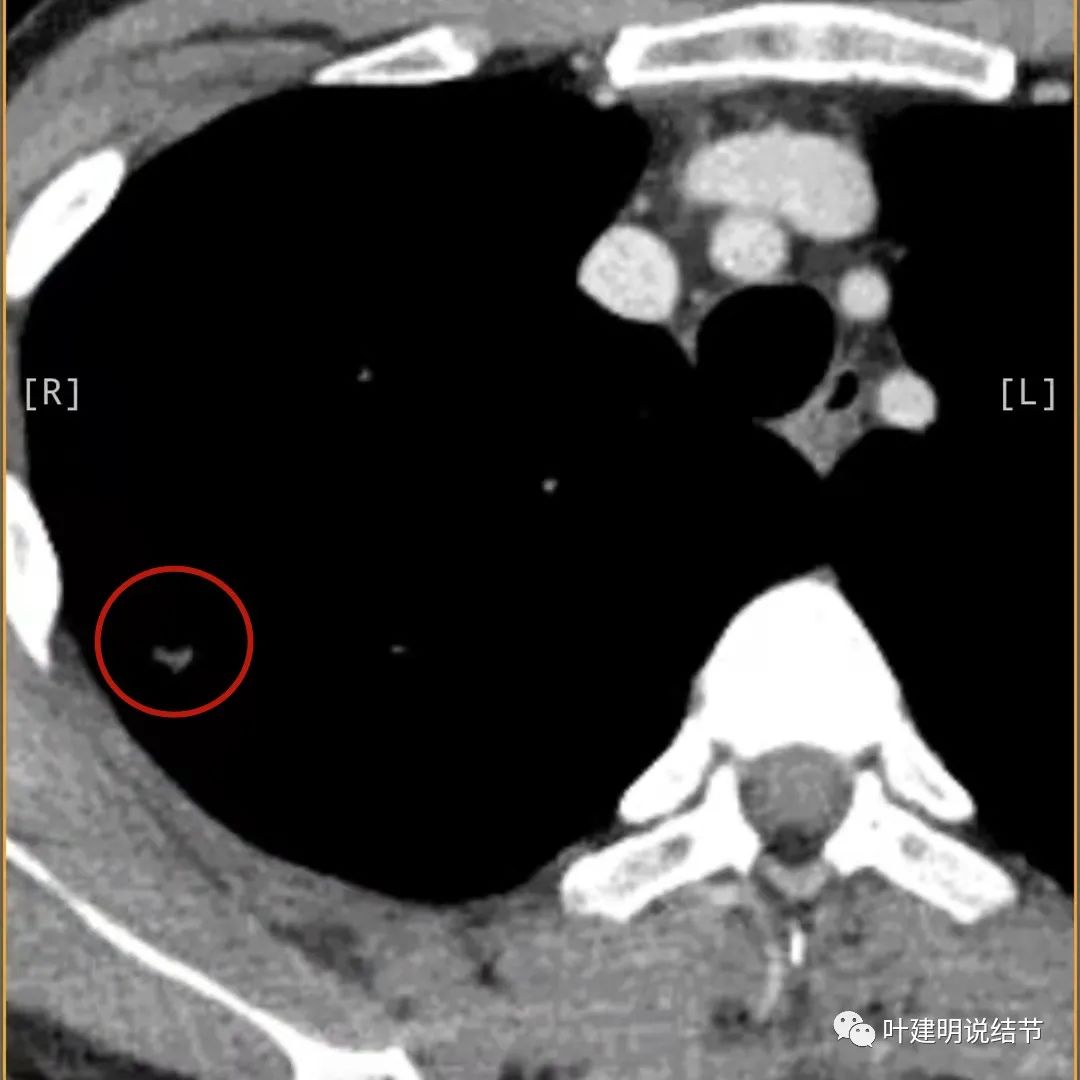

纵隔窗无钙化

蓝色箭头所指处居然有低密度影,难道是坏死?因为比肌肉密度低,也无强化,况且主病灶的中间也有个低密度的小点状